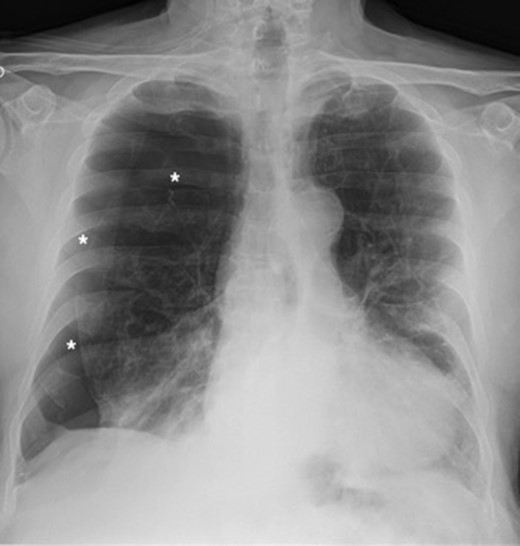

A 73-year-old male patient with a clinical history of COPD, lung emphysema and a 30-year smoking history was admitted to the ED due to a 24-h clinical picture of dyspnea immediately following a sudden bout of dry coughing. Physical examination showed a dyspneic patient, tachypnea of 25 rpm, heart rate of 85 bpm and blood Pressure of 135/75 mmHg along with central cyanosis. Chest exam showed a hyper-resonant right hemithorax along with reduced breath sounds. Initial chest X-ray revealed a large right-sided pneumothorax (Fig. 1). A right chest tube was placed in the ED. Emergency echocardiogram had no significant findings and spirometry showed suspected patterns of obstruction. Following patient stabilization, a high-resolution chest computed tomography (HRCT) was performed revealing extensive pan lobar emphysema throughout both lungs, para septal emphysema in both the anterior upper lobes and herniation of a left lung bullae through the anterior mediastinal pleura along with a right-sided pneumothorax with the chest tube in place with persistent air space (Fig. 2). The patient was taken to surgery where a right video-assisted thoracoscopic (VATS) approach showed severe lung emphysema and a contralateral herniated left lung bulla through the mediastinal pleura anterior to the pericardium (Fig. 3). Right pleurodesis was performed using Talc and a left posterior thoracoscopy showed a severe emphysematous left lung with a lingular herniated bulla to the right hemithorax through an anterior mediastinal pleural defect along with pleural adhesions (Figs 4 and 5). Thoracoscopic hernia reduction was performed along with bullectomy using 60 mm mechanical sutures (Fig. 6). Chest tubes were removed on POD 3 (right) and POD 4 (left). The patient had significant respiratory improvement and was discharged on POD 5.

High-resolution computed tomography (HRCT) thorax showing trans‐mediastinal herniation of pulmonary bulla with right pneumothorax.